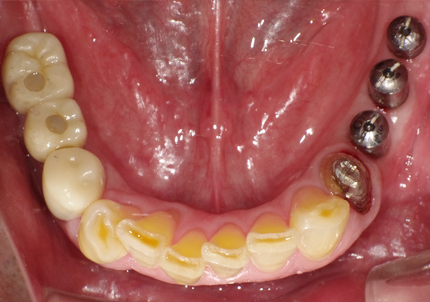

1.初診時口腔内写真(2014年6月)

2.治療終了(2016年6月)

・上顎補綴物再製

・右下2本インプラント

・左下ジルコニアクラウンブリッジ

10.口腔内写真(2022年2月)

特に問題無く経過はとても良いです。

患者様ご本人も「良く咬めてとても良い」と満足されています。

11.口腔内写真(2025年6月)

右下2本初診より9年経過、左下3本埋入後4年経過、ともに経過良好。